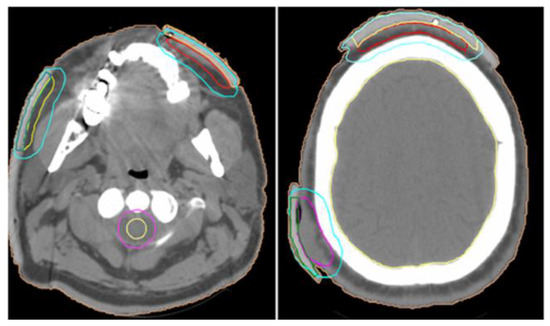

In May 2022, the oncology board at our radiation therapy center examined the patient and decided to enroll him in a palliative radiation therapy program for the treatment of localized lesions on the face and scalp (Figure 1), using LINAC ELEKTA 6 MV with 3DCRT technique on the following PTVs: PTV right frontal (TD=30 Gy/15 fractions, D/fr=200 cGy), PTV right parietal (TD=30 Gy/15 fractions, D/fr=200 cGy), PTV left oral commissure (TD=30 Gy/15 fractions, D/fr=200 cGy) (Figure 2).

Figure 2. PTV left oral commissure (a), PTV right frontal (b), PTV right parietal (b).